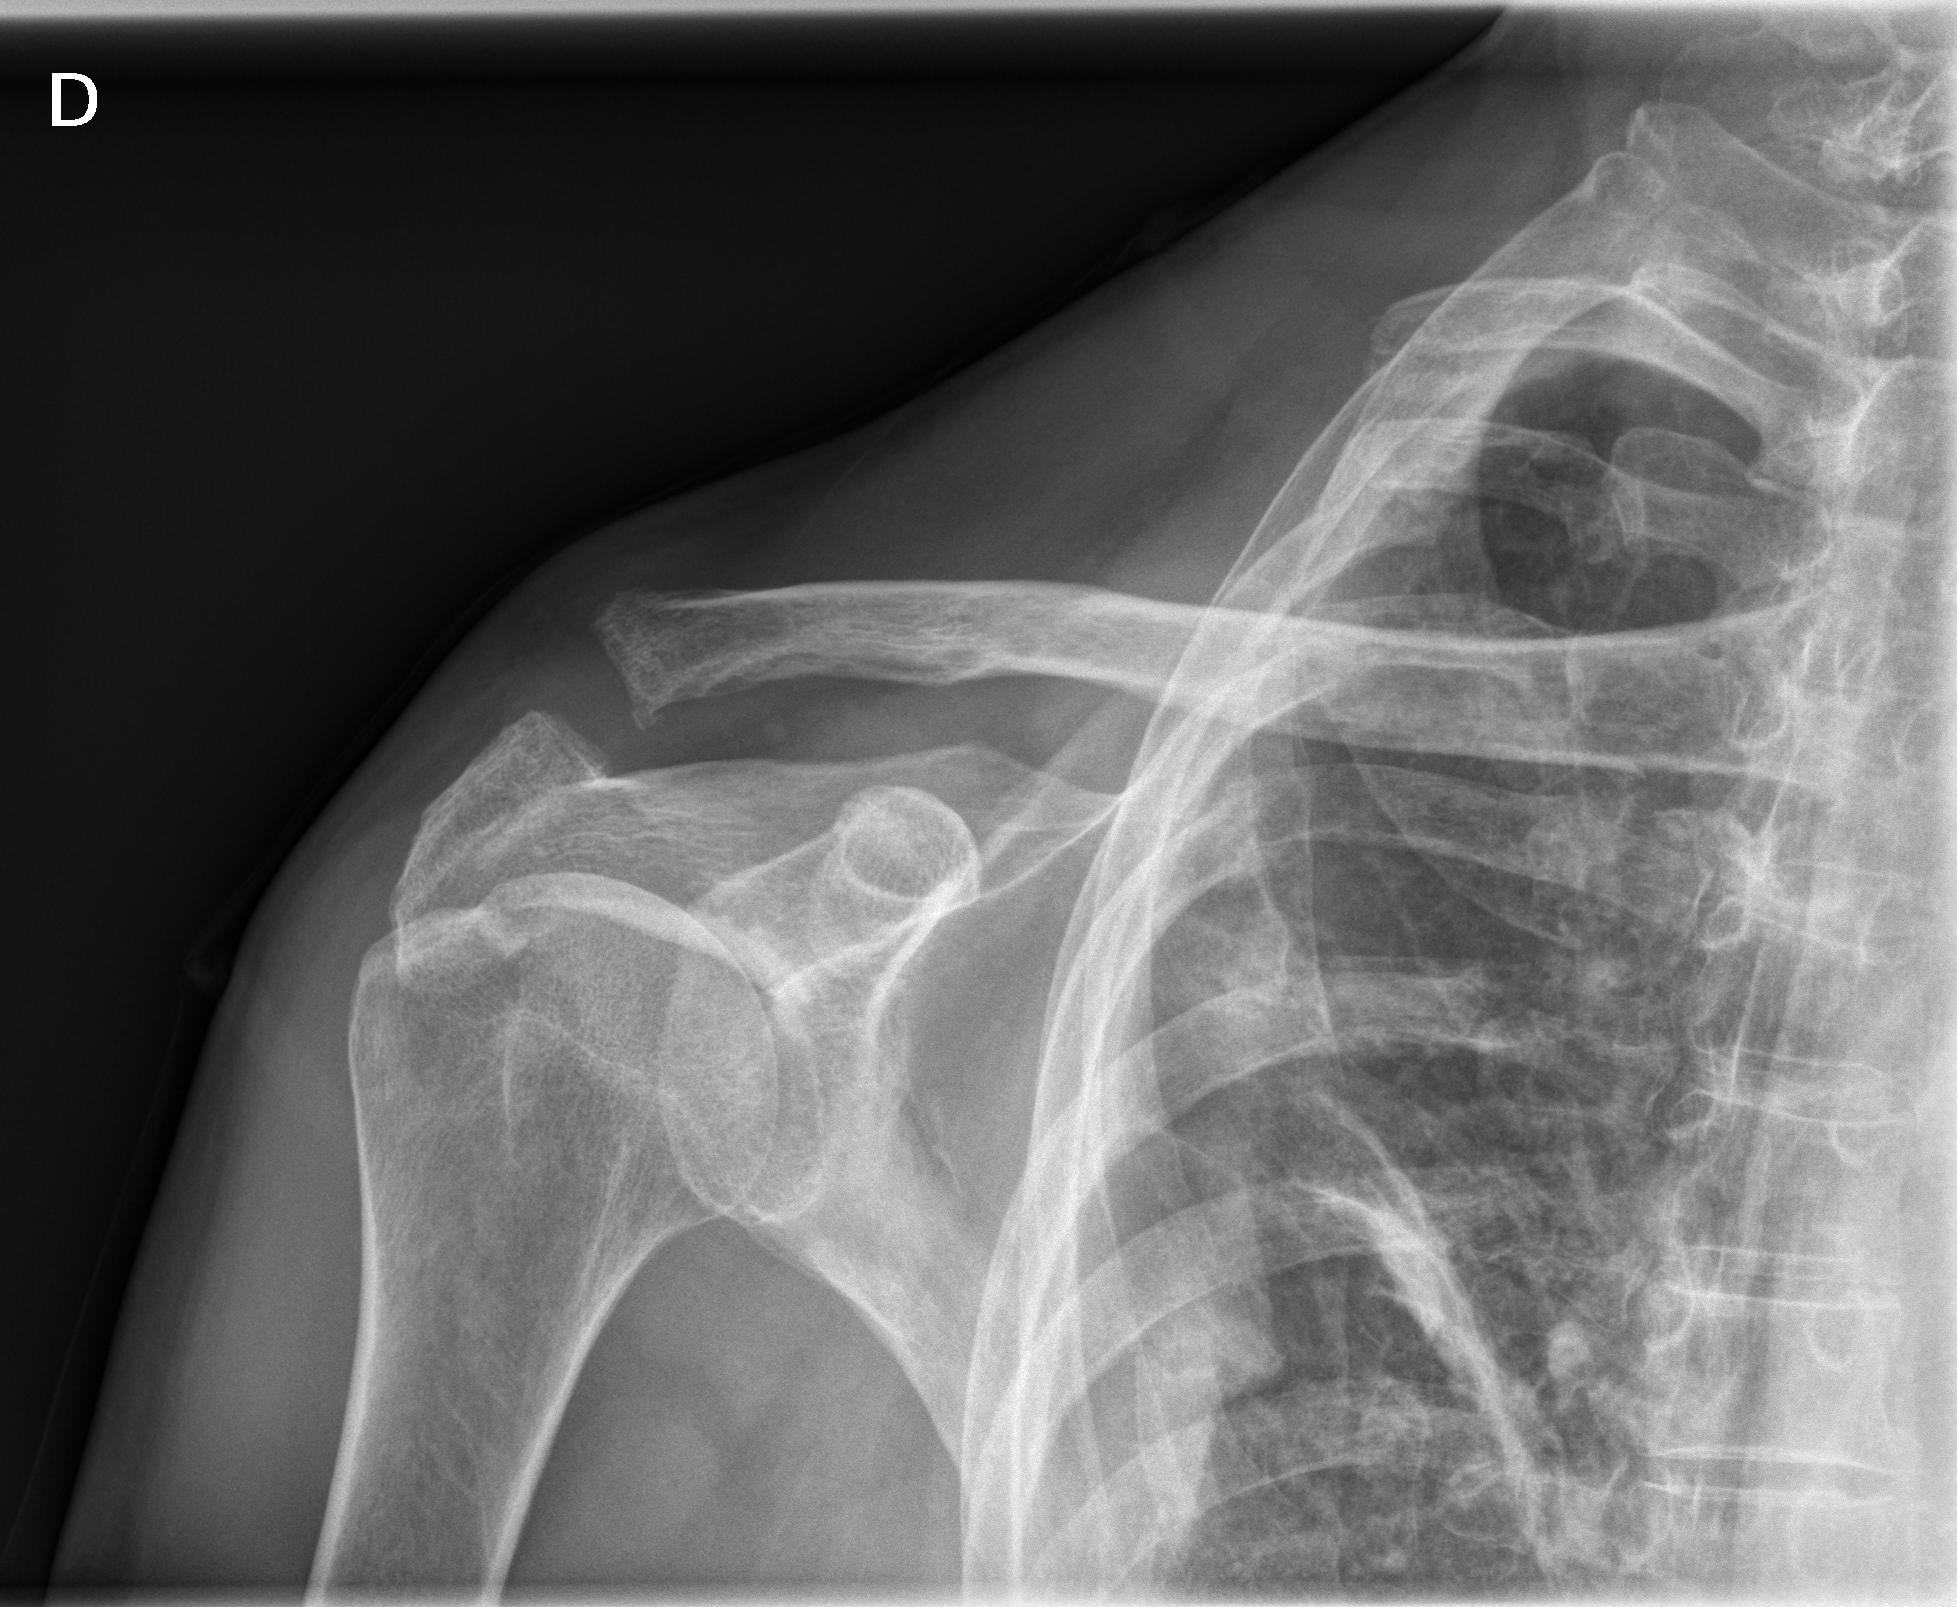

1 Hombro der.